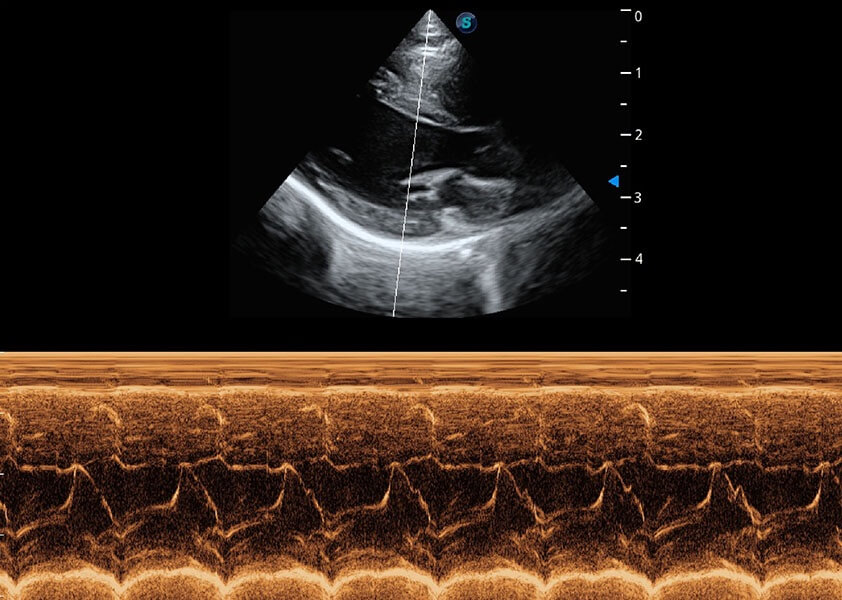

心脏解决方案

ProPet 60 配备了丰富的心脏探头群、先进的成像技术和专业的心脏测量工具,可帮助动物医生为不同体型和生理结构的动物提供心脏和心肌功能的全面评估。

• TDI 组织多普勒成像

实时用颜色表示心肌组织运动,观察和定量组织的运动情况,对快速检测与评估心肌的灌注和活性、电传导及心肌收缩和舒张功能等均能提供重要的诊断信息。

• MQA 心肌定量分析

通过心肌识别技术与二维斑点追踪技术相结合,对心脏的超声图像进行量化分析。计算心肌17个节段的应变、应变率、速度、位移等,并通过牛眼图的形式进行呈现。

• AMM 解剖M型

通过360度任意调节3条M型取样线,在同一心动周期上观察心脏不同位置的运动曲线,得到准确的心功能测量数据,有效评估心肌运动及左心室功能。

优异的基础图像

(犬)心脏组织多普勒

(猫)二尖瓣M型